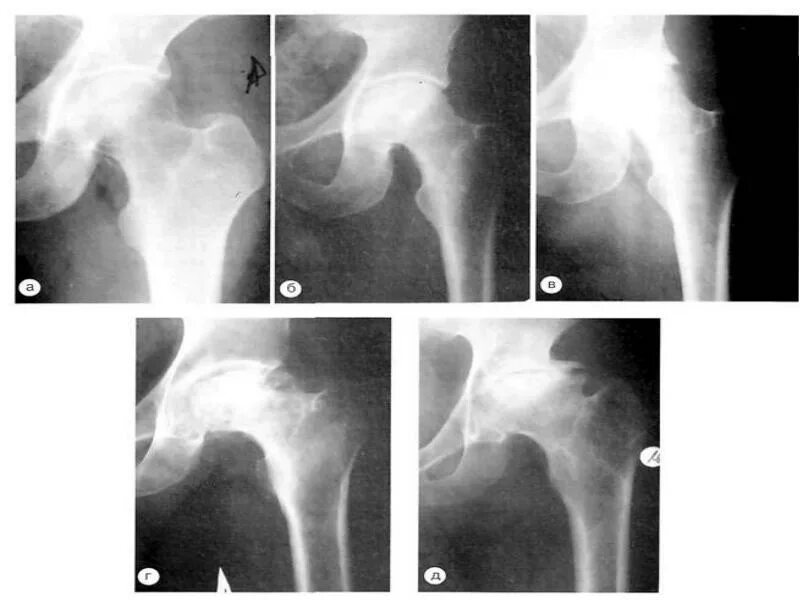

Боли при некрозе тазобедренных суставов